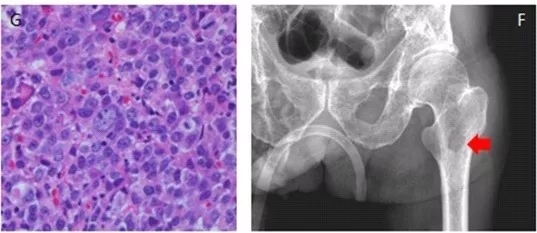

骨痛是本病的一个常见症状。疼痛的程度轻重不等,早期往往是暂时的、轻度的,随着疾病的病程进展可以逐渐变为持续而严重。如果疼痛剧烈或者骤然加剧,一般提示发生了病理性骨折。

多发性骨髓瘤最临床表现除贫血、出血、感染等临床表现外,可有蛋白尿(甚至尿毒症)、骨痛(重者会有骨折)、高凝状态或静脉血栓等其它临床表现。